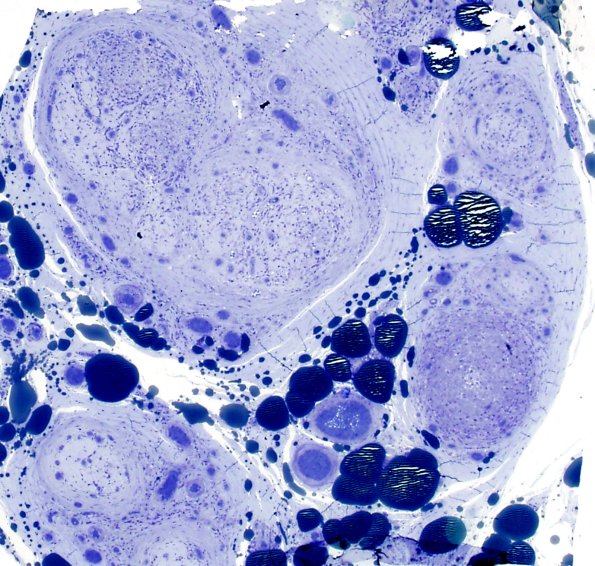

Low magnification images showing marked loss of large and small myelinated axons. (plastic sections)